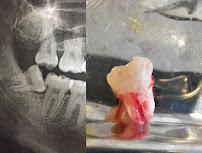

• Dental Emergency Care — immediate assessment and treatment for acute dental pain, dental abscesses, fractured teeth, dislodged fillings, post-surgical complications, and other urgent oral conditions.

• Emergency Extractions — urgent removal of teeth that cannot be saved or that are causing acute pain or infection.

The clinic's location within the España 460 building places it in an easily identifiable and accessible part of central Temuco, reducing the logistical barriers for patients arriving in discomfort who need to locate the clinic quickly. Diagnostic imaging support is available to guide treatment decisions, ensuring that emergency interventions are based on accurate clinical assessment rather than assumption.